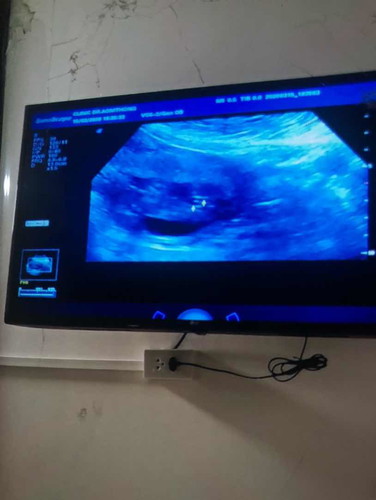

รู้เพศน้องยังคะ 18+2 วีค บ้านนี้เห็นจิ๊มิเป็นกลีบเลยค่าาา?? กำหนดคลอด 15 สิงหา 63